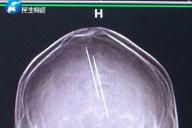

Игорь Зур Дональд Трамп налоги журналисты СМИ | Средства массовой информации финансы В миреИз-за дорожно-транспортного происшествия женщина узнала, что она на протяжении 30 лет носила в своей голове две швейные иглы.

Яна Русая женщина врачи полиция преступление врач ОбществоЧлен президиума Координационного совета Мария Колесникова написала еще одно письмо из тюрьмы.